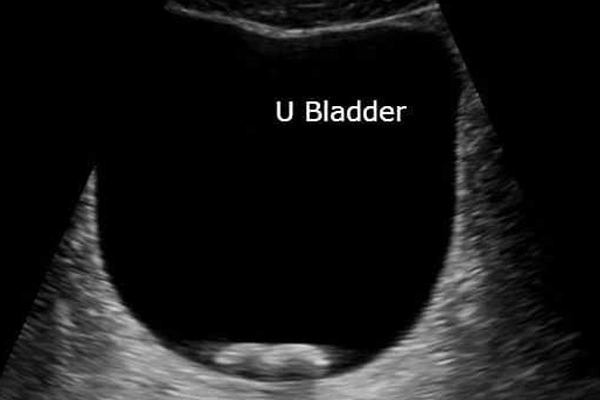

• Ultrasound: Ultrasound is a simple and painless test that helps detect bladder stones and shows their size and position inside the bladder.